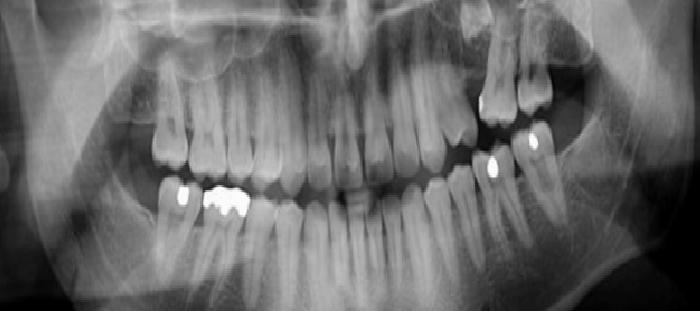

Diş filmleri, çürüklerin tespitinden daha fazlası demektir. Örneğin, filmler süren daimi dişlerin takibi, kemik hastalıklarının tespiti, dental kazaların boyutunu ölçülmesi veya ortodontik tedavinin planlanması için kullanılır. Dental filmler, diş hekimine klinik muayene sırasında tespit edilemeyecek olan durumların değerlendirilmesinde ve tedavi planlamasına izin verecektir. Eğer dişsel problemler erkenden tespit ve tedavi edilirse, bu daha rahat ve kabul edilebilir olacaktır.